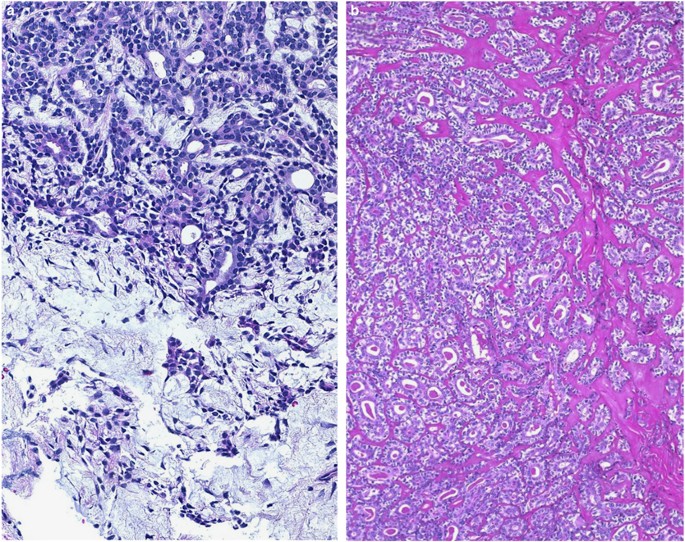

EMCA do show a good deal of overlap with the other biphasic tumors. EMCA can resemble cellular PA, but importantly, it is distinguished by its multinodular infiltrative growth and sclerosis (Figure 5b). Cellular PA may show sclerosis, but do not infiltrate. In addition, the abluminal myoepithelial cells are smaller, less distinct, and characteristically ‘stream’ into a chondromyxoid stroma (Figure 5a). EMCA may also overlap with tubular patterned ACC. However, ACC is more infiltrative, and composed of more angulated hyperchromatic nuclei with scant cytoplasm. In addition, ACC tubules will cleft from the basement membrane. EMCA may show cell dyshesion, but is between the ductal and myoepithelial cell layer rather than the basement membrane. Immunoprofile of both tumor types shows considerable overlap, including c-kit reactivity. From a molecular standpoint, ACC are defined by MYB alterations,16 while EMCA often show RAS mutations.20

Distinction between EMCA and cellular PA. (a) Cellular PA is biphasic and bilayered but well demarcated, and the myoepithelial cells often stream into a chondromyxoid stroma as seen here. (b) EMCA is more characteristically multinodular and tends to show more plump polygonal abluminal myoepithelial cells with bilayered tubules surrounded by sclerotic stroma rather than myxoid stroma.